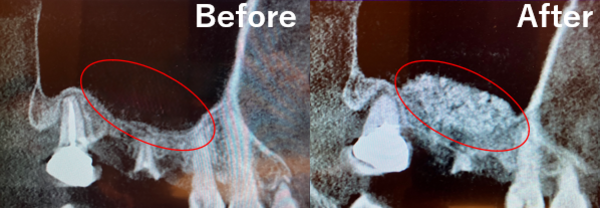

なお、抜歯前に撮影したCT画像では、副鼻腔内膜が歯由来の感染症で炎症を起こし、かなり肥厚しているのが確認されたのですが、サイナスリフト前に再度CTを撮影したところ、肥厚は消失し綺麗になっているのが確認できました。

白っぽく膨らんで見える部分が肥厚です。抜歯後には感染が除去されたことにより肥厚が綺麗になくなっていました。